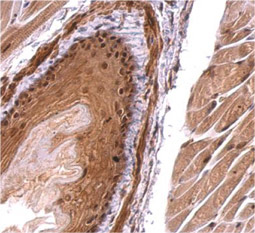

IDH1 antibody

(GTX629818)